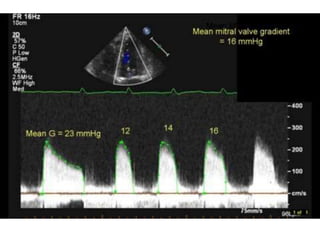

Pressure gradient (Level 1

Recommendation).

CW doppler signal is obtained in A4CV and

traced

Caution:

1. Gradient is influenced by HR, cardiac output,

MR, VSD

2. In patients with atrial fibrillation, mean

gradient should be calculated as the average

of five cycles with the least variation of R–R

intervals and as close as possible to normal

heart rate

Pressure gradient (Level1 Recommendation). CW doppler signal is obtained in A4CV and traced

Caution: 1. Gradient isinfluenced by HR, cardiac output, MR, VSD 2. In patients with atrial fibrillation, mean gradient should be calculated as the average of five cycles with the least variation of R–R intervals and as close as possible to normal heart rate